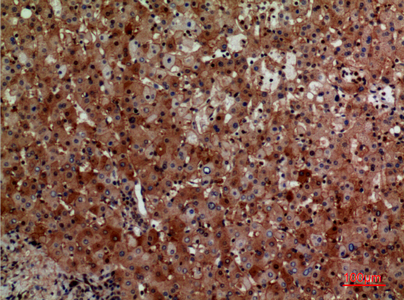

WB,IHC-P,IF-P,IF-F,ICC/IF,ELISA

WB 1:500-1:2000, IHC-P 1:100-300, ELISA 1:20000, IF-P/IF-F/ICC/IF 1:50-200